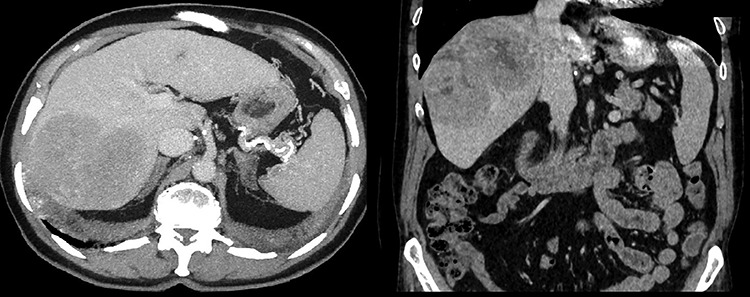

A 64-year-old male with severe ischemic cardiomyopathy underwent implantation of an LVAD (Heart mate II™, Abbott, Chicago, USA) in 2012. Decision of LVAD as destination therapy instead of heart transplantation was made due to history of hepatitis B infection, chronic kidney insufficiency and COPD. Patient remained in good condition with normal LVAD function. Further history included atrial fibrillation and pulmonary embolism. In 2019, hepatocellular carcinoma (HCC) was incidentally detected in the postero-lateral sector of the liver. Preoperative LiMax-Test [2] revealed good liver function (316 μ/kg/h), MELD XI Score was 15 without signs of portal hypertension. Staging revealed no distant metastases and confirmed local resectability (comp. Fig. 1).

Figure 1.

Preoperative CT scan revealing suspected malignancy